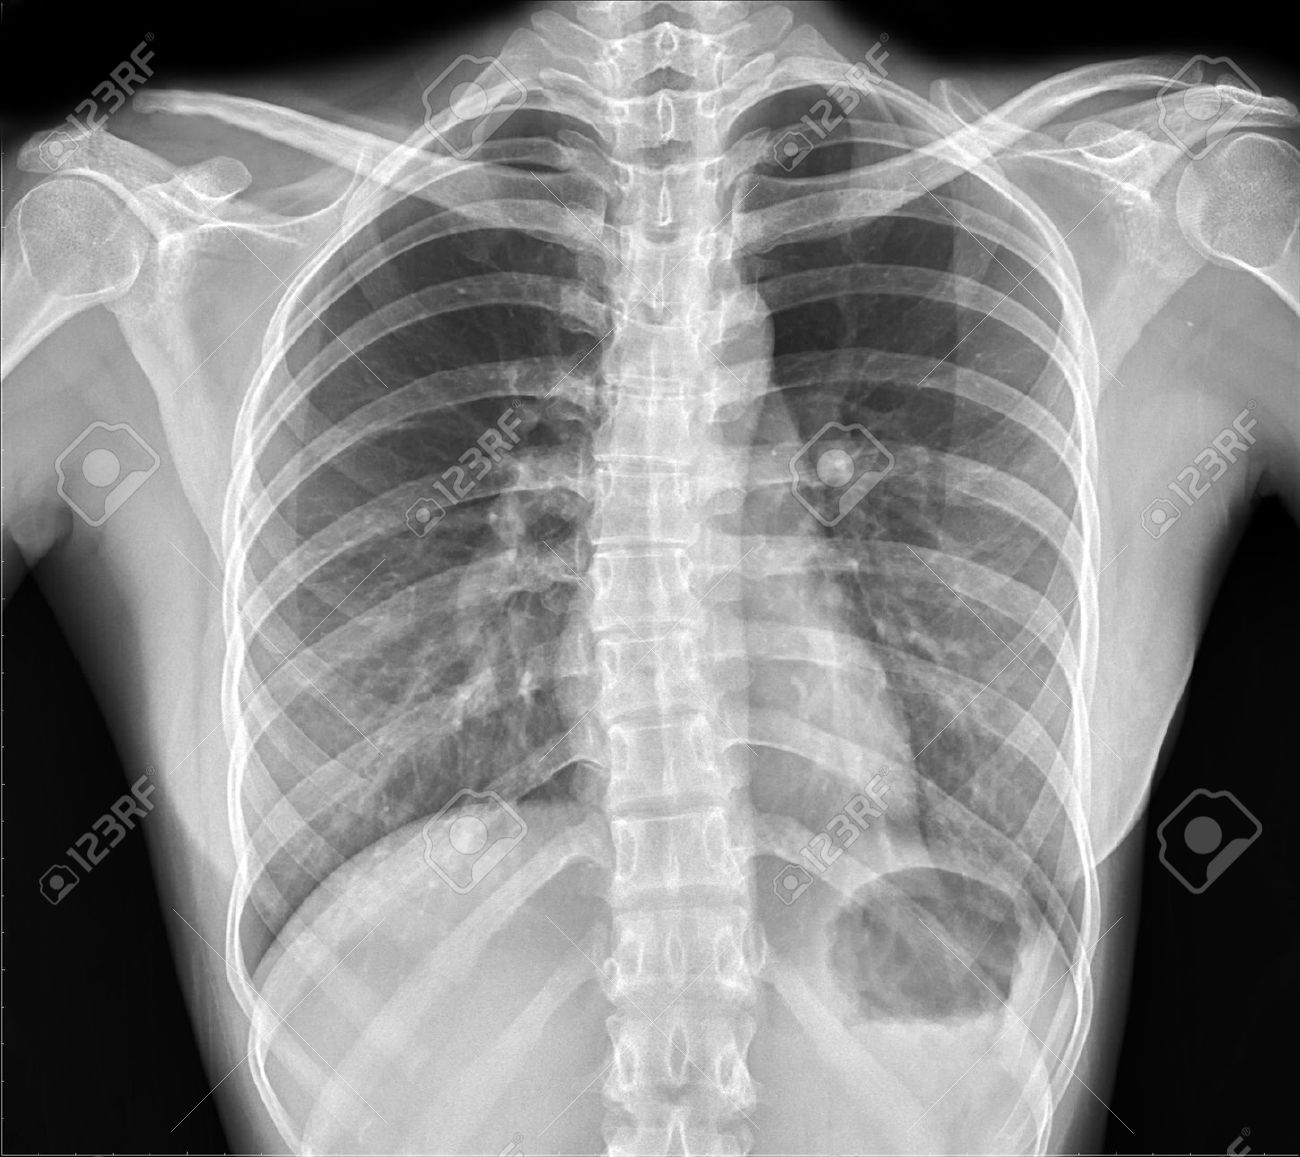

X-ray Wallpapers - Wallpaper Cave

wallpapercave.comwallpaper ray wallpapers radiology bone xray background desktop hd knuckle mystery cracking cracks math breakdown needs bit building first getty

wallpapercave.comwallpaper ray wallpapers radiology bone xray background desktop hd knuckle mystery cracking cracks math breakdown needs bit building first getty

X-ray Wallpapers - Top Free X-ray Backgrounds - WallpaperAccess

wallpaperaccess.comray acromioclavicular radiology separated radiopaedia rays dislocation knochenkrebs grafi radiologie injury clavicola ursachen typen symptome krebs radiografia quiz medicare dores

wallpaperaccess.comray acromioclavicular radiology separated radiopaedia rays dislocation knochenkrebs grafi radiologie injury clavicola ursachen typen symptome krebs radiografia quiz medicare dores